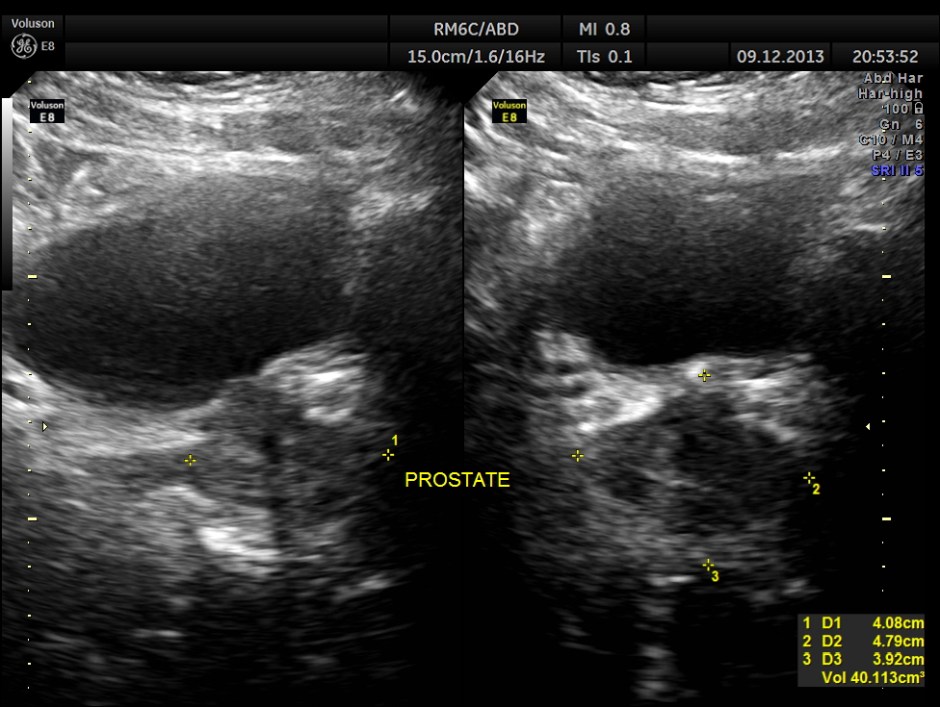

Urinary bladder and prostate are shown below. Mild prostatomegaly seen.